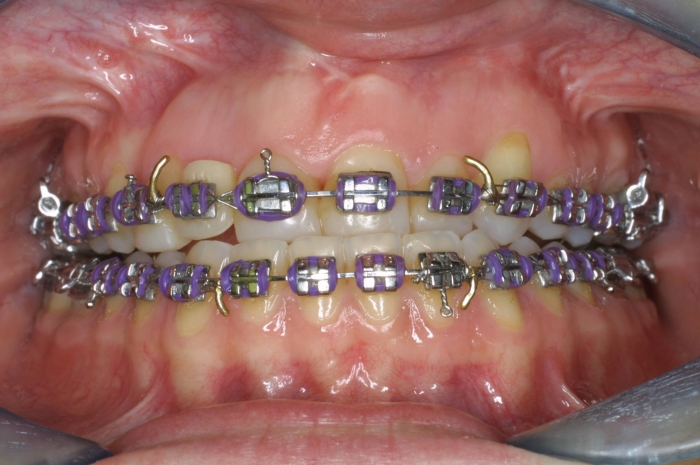

Imagem após cirurgia ortognática - Clínica Cliniface

Imagem após cirurgia ortognática